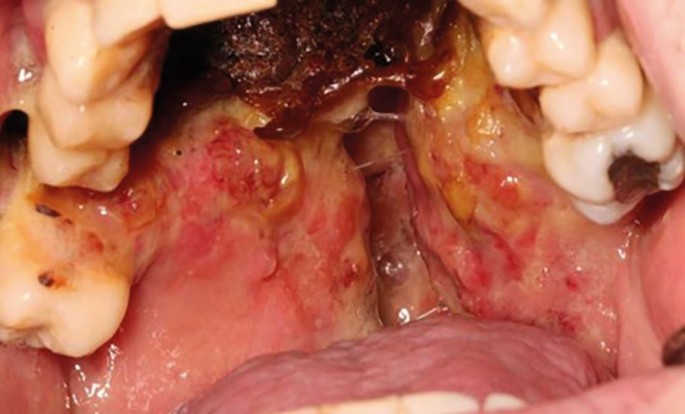

On examination, there was a loss of the nasal columella and saddle nose deformity. Intra-orally, there was complete erosion of the hard and soft palate and destruction of the nasal septum, with superimposed overgrowth of tissue and suppuration extending from the anterior hard palate posteriorly toward the oropharynx. The defect was surrounded with florid angiomatous tissue and bordered with crusted necrotic tissue (Fig. 5, Fig. 6). All remaining maxillary teeth were mobile (Fig. 7).

On examination, there was marked flattening of the bridge of the nose. There was no evidence of cervical lymphadenopathy. Intra-orally, there was a palatal fenestration communicating with the nasal cavity (Fig. 6).

Palatal defect associated with cocaine abuse